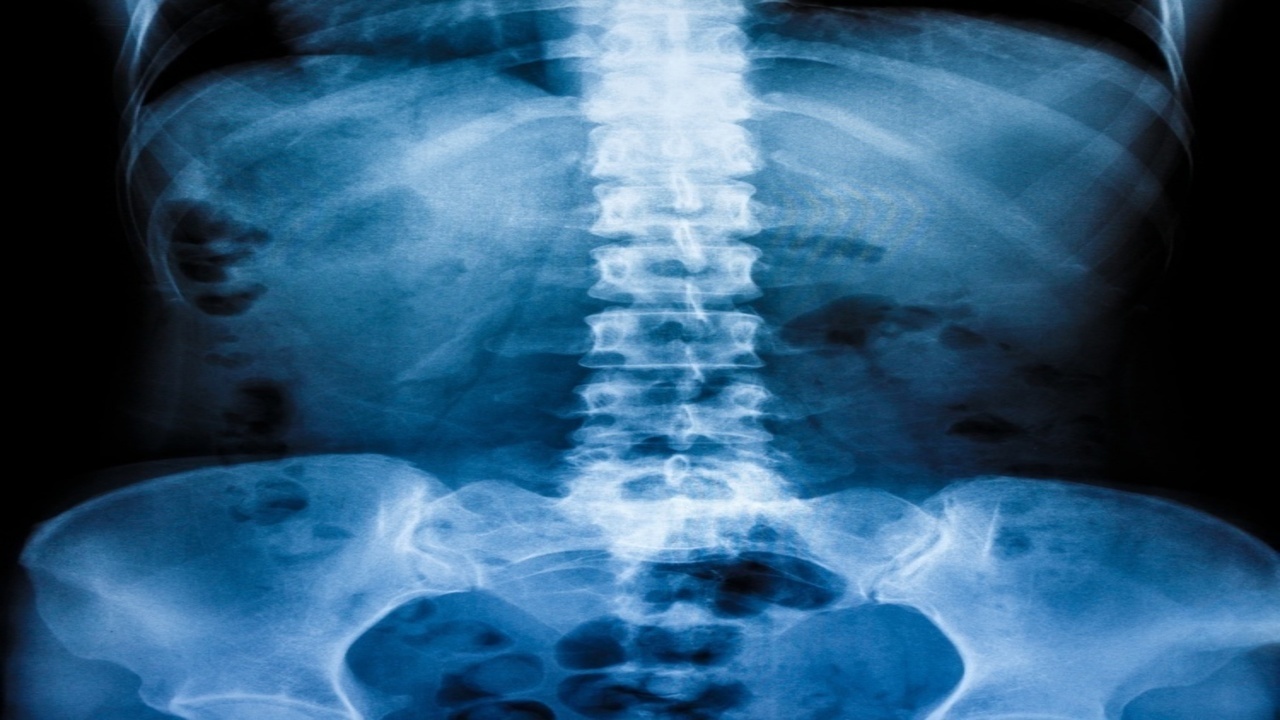

腰椎の間にある椎間板は、クッションとして衝撃を吸収しています。

加齢や負担の蓄積により椎間板が変性し、中の髄核が飛び出して神経を圧迫すると、腰や脚に強い痛み・しびれを引き起こします。

骨盤・背骨の歪み

猫背・反り腰・骨盤の傾きで腰椎にアンバランスな力が集中。